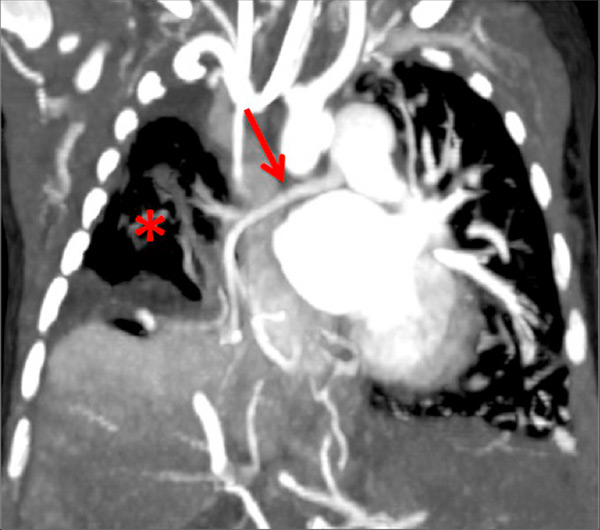

Figure 6

Perfusion heterogeneities in idiopathic pulmonary artery hypertension (stars) in two different patients (A/B). The dilatation of the arteries in pulmonary hypertension (arrows) is not always observed depending on the severity of pulmonary hypertension.